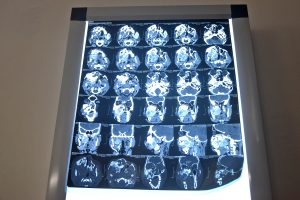

Exploraciones de Melon

La operación fue realizada por el Dr. Macho, un experimentado cirujano maxilofacial, que extirpó cuidadosamente el tumor del maxilar superior de Mellon preservando la mayor cantidad posible de tejido sano y hueso. Gracias a la habilidad del equipo quirúrgico, la operación fue un éxito, y Melon se está recuperando bien y ya come más cómodamente, habla sin esfuerzo y ya no soporta dolores ni molestias durante tanto tiempo.